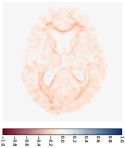

Figure 4 shows the prediction results of our model for one subject sample from the non-demented test group in the OASIS dataset. This subject has MRI scans at 80, 81, 85, and 86 years old, and there are missing images at multiple time points. We predict one image scan per year from 80 years to 88 years, including those missing ones, as shown in the second row of Fig. 4. Since the brain changes are quite subtle (see the first row of Fig. 5), we also plot the deformation map at each time point, as shown in the last row of Fig. 4. These deformation maps show the estimated changes in the brain MRIs. As we can see, the grids are expanding, especially around the brain ventricle region. This expanding ventricle indicates our model captures the degeneration process of the ventricle in the brain, i.e., an enlarging ventricle. Figure 5 shows the image difference between predicted images and their corresponding image scans in the second row. Compared to the first row that shows image difference of follow-up scans with respect to the first one, the prediction difference is relatively smaller, especially around the ventricle region. Table 1 reports the means and standard deviations of the prediction difference for all images in the non-demented and demented groups, which are 5.8616e-41.0703e-4 and 6.1105e-41.9793e-4, respectively.

Apart from the subject-specific image prediction, our model can also estimate a group trajectory by predicting forward and backward image sequences for the atlas (the mean image) built for that group. Figure 6 demonstrates the mean trajectory estimated for the demented group. We first estimate the mean image using the unbiased atlas building algorithm (Joshi et al., 2004). This atlas is our baseline input, and we predict vector momenta forward to generate future image scans. By using the negative vector momenta, we shoot the atlas backward and generate previous image scans. From the predicted images within 25 years (every three years shown in Fig. 6), we can recognize the brain changes, in particular, the enlarging ventricle over the years. The deformation maps shown in the second row are generated starting from the atlas in the middle. Therefore, they show the expanding grids in the forward sub-sequence and the compressed grids in the backward sub-sequence.